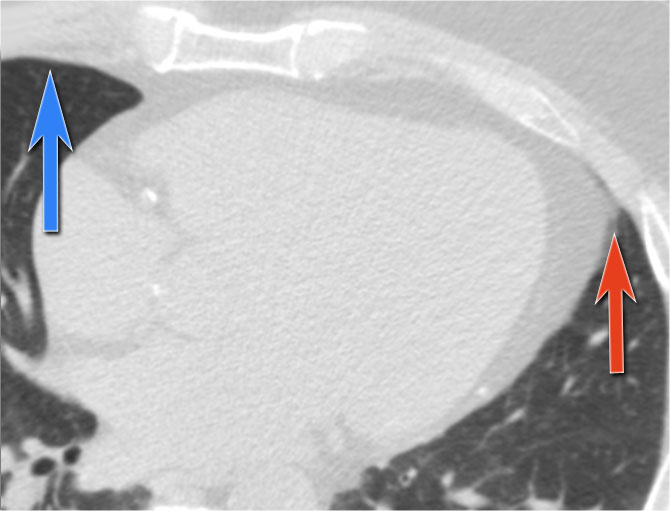

CT correlation

The explanation for the cardiac incisura is seen on this CT-image.

At the level of the inferior heart, the right lower lobe (blue arrow) is often seen extending more anteriorly than the left lower lobe (red arrow) , explaining the asymmetry of the cardiac incisura.